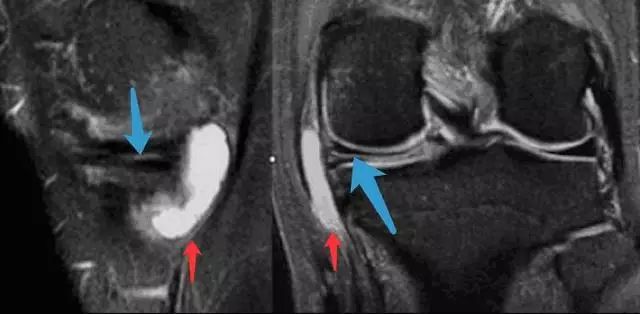

图 14 半月板根部撕裂和半月板膨出

左图:冠状面可见内侧半月板后角在与根部(与胫骨连接的部位,白色大箭头)交接的部位有一个全层的撕裂(白色小箭头),可与对侧正常结构对比(黑色箭头)。右图:冠状面可见内侧半月板体部膨出关节(白色箭头),半跨与胫骨平台上。本图还可看到内侧股骨髁的关节软骨有相较于外侧的退行性缺失。